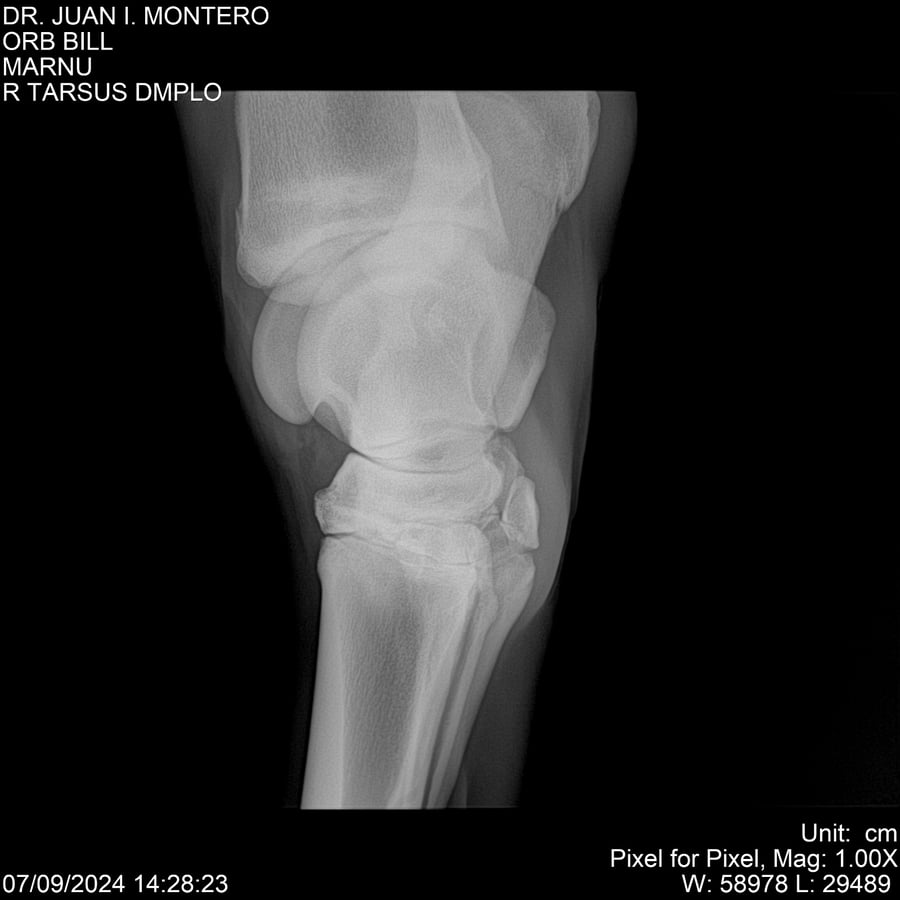

LOTE 7, ORB BILL 🔥 🔥 🔥 Lote Anterior Volver al remate Lote Siguiente Ficha Contacto Montevideo - Ficha del Lote Identificador: #282523 Categoría: Yeguarizos Montevideo - 83 Visualizaciones ClicData Contacto Empresa: Abelenda N. R., Walter Hugo Nombre*: Teléfono* : E-mail* : Mensaje Enviar Registrese gratis Este contenido Exclusivo está disponible sólo para usuarios registrados Ingresar